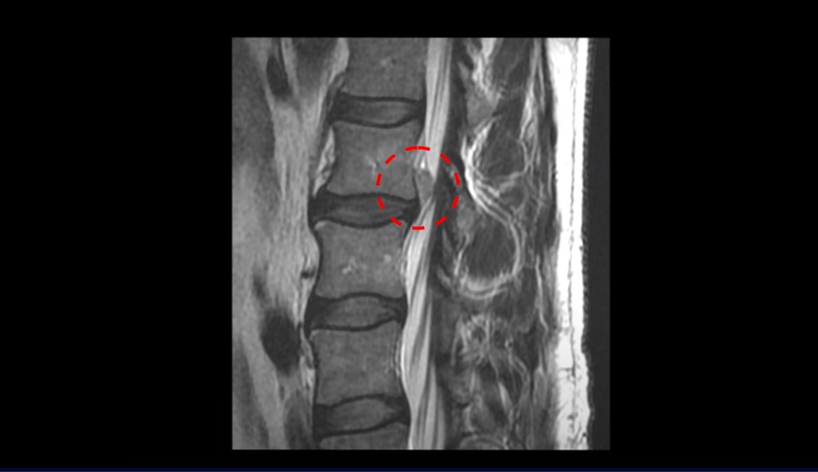

우선 이분 MRI를 보면 디스크가 심하게 터져 위로 밀려 올라가 있습니다. 신경가지가 나가는 구멍을 보시다시피 막고 있으니까 마비 증상과 방사통이 있습니다.

그런데 저희 모커리는 이렇게 심하게 파열된, 특히 수핵이 밀려 나와서 아래로 흘러내리거나 위로 올라가 버릴 정도의 심한 파열일수록 오히려 치료가 더 쉽고 잘 된다고 여러 영상을 통해 지속적으로 말씀드리고 있습니다. 그 이유는 디스크 파열이 심하면 심할수록 밀려 나온 수핵이 깨끗이 흡수되어 없어질 가능성이 높기 때문입니다. 그럼 이분은 치료가 끝나고 6개월 후에 MRI를 다시 찍으셨는데 과연 밀려 나온 디스크 수핵이 전부 다 깨끗이 흡수되었을까요? 이분이 치료 끝나고 6개월 후에 찍은 MRI 영상은 치료 후 결과영상에서 보실 수 있습니다.